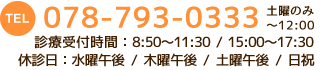

ドライアイ

ドライアイは、目の表面を保護している涙の量が不足したり、涙の質が低下する病気です。

涙は涙腺でつくられ、まばたきの度に、目の表面を潤す役割を持っています。

その内10%が蒸発、残り約90%が涙点という穴から排出され、涙少管を通り、鼻へと流れ出ていきます。

| 検査 |

|